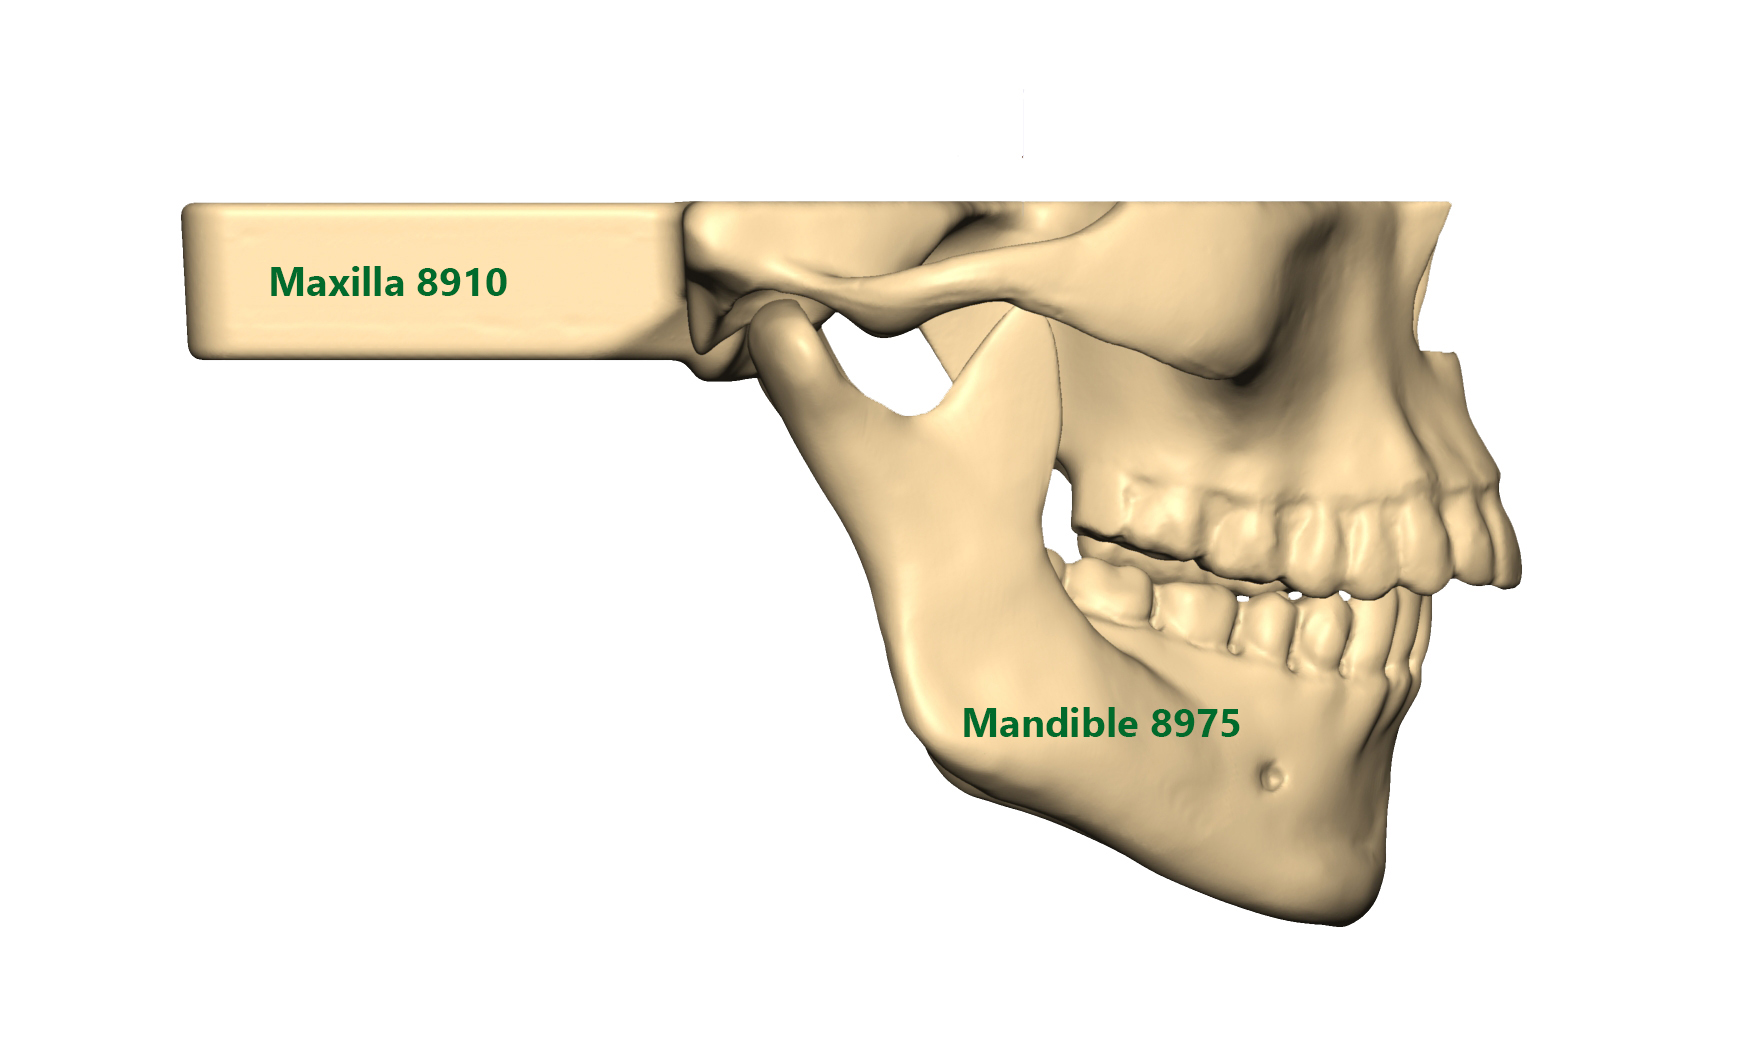

Mandible and Maxilla models with Easy Clip

SYNBONE’s new Mandible and Maxilla models with easy clip mechanism offer the highest flexibility when combining the products together. The Mandibles do also correspond to our 8200 / 8700 and 8800 Skull models.

You can choose from standard, overbite or underbite situations for your orthognathic surgery education. We offer intact, fractured or prefractured models for your LeFort I and BSSO workshops. Thanks to the drill holes between each tooth all models can be used for cerclage wiring.

Our Maxillas with Easy Clip mechanism correspond to the 8900 and 8950 Mandible series. Rubber brackets allow a firm hold of the mandibles.

All Mandibles with Easy Clip mechanism correspond to our 8200 / 8700 and 8800 Skull models as well as 8910 and 8915 Maxillas.

Reusable cerclage wiring alternative clip for Maxilla/Skull and Mandible fixation. Also ask for our regular / overbite and underbite OP-Splints.